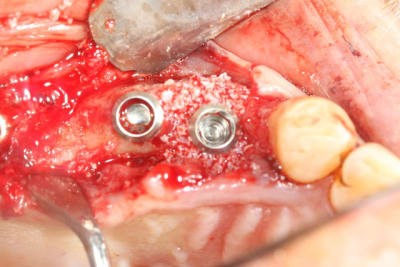

voici mon premier cas d'Extraction implantation Immediate...

1/as tu place une membrane pour ta rog?

2/ pourquoi le faire en un temps? Le risque d'echec de la rog est majore dans cette approche je pense?

Justement cartman...

J'avais prévu en amont; bio oss et membrane.

En examinant la paroi vestibulaire de l’alvéole après extraction...j'ai pensé que la résorption faisant l'option implantaire serait plus compliquée par la suite. J'ai donc posé l'implant en 24;

A posteriori je me dit que j'aurai du poser la membrane autour de l'implant pour éviter la compétition cellulaire et optimiser mon comblement.

On va dire que j'ai été ptit bras sur ce coup.

Ici, pas besoins de membrane car ton défaut osseux est à 4 parois

dommage que tu sois si timide pour la longueur des implants, y'avait de quoi mettre un peu plus long et faire une mise en esthétique immédiate

oui t'as raison, mais comme je ne suis encore rompu au bon positionnement tridimensionnel des implants, j'ai préféré me laisser un peu de marge au cas ou je dévie...